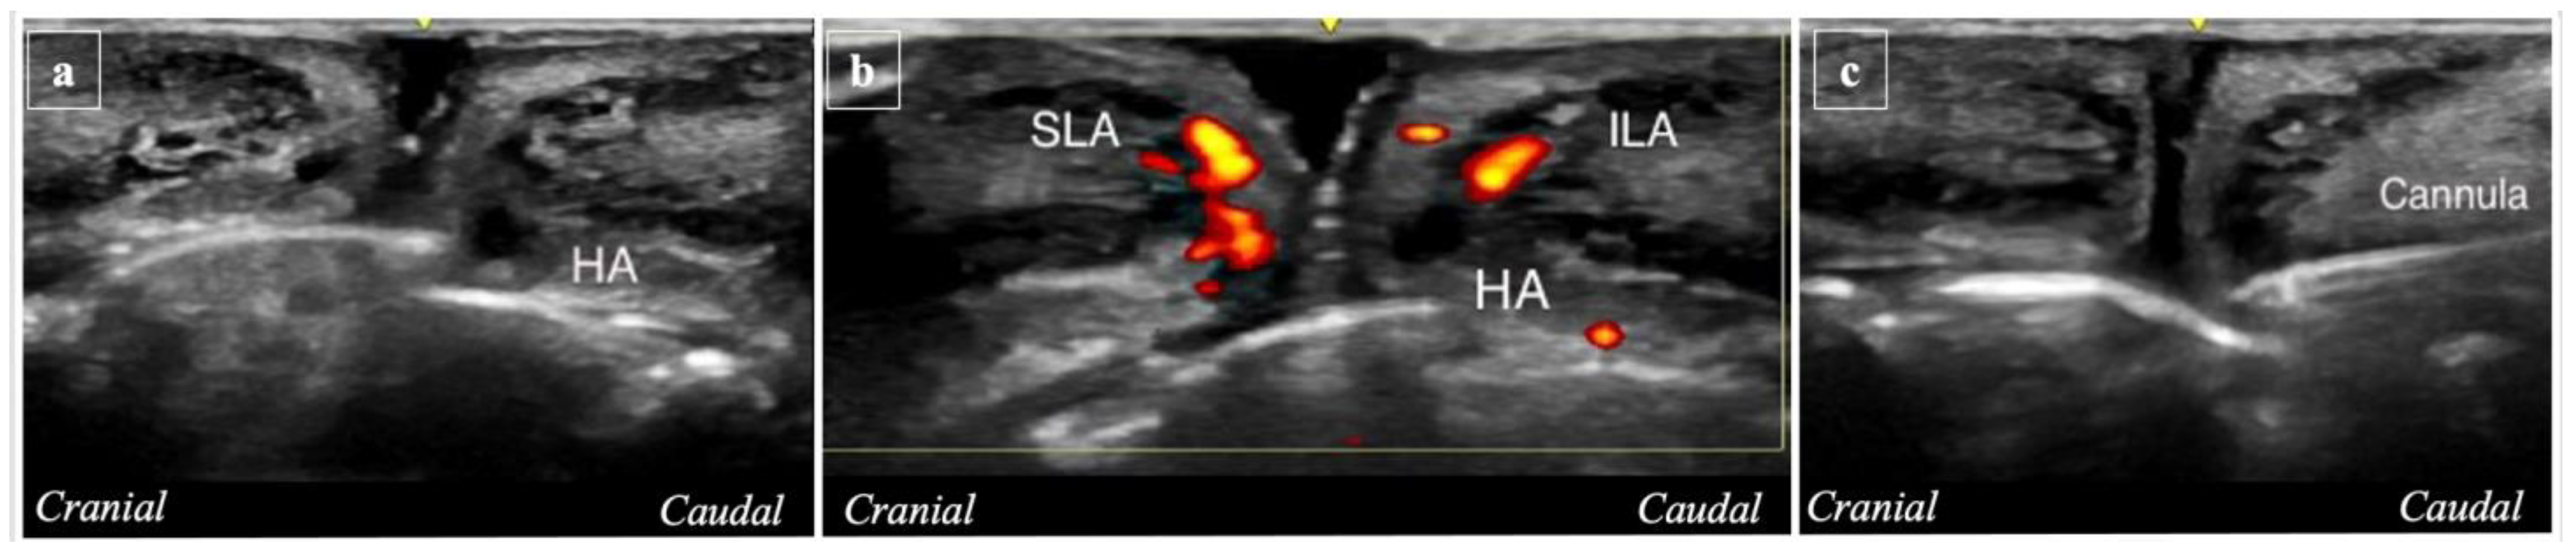

2.3. Ultrasound Analysis

- (i)

- (ii)

- Post-procedure imaging (T2) involved capturing new images in the same vertical positions in A1, A2, A3, A4, and A5 (Figure 7).